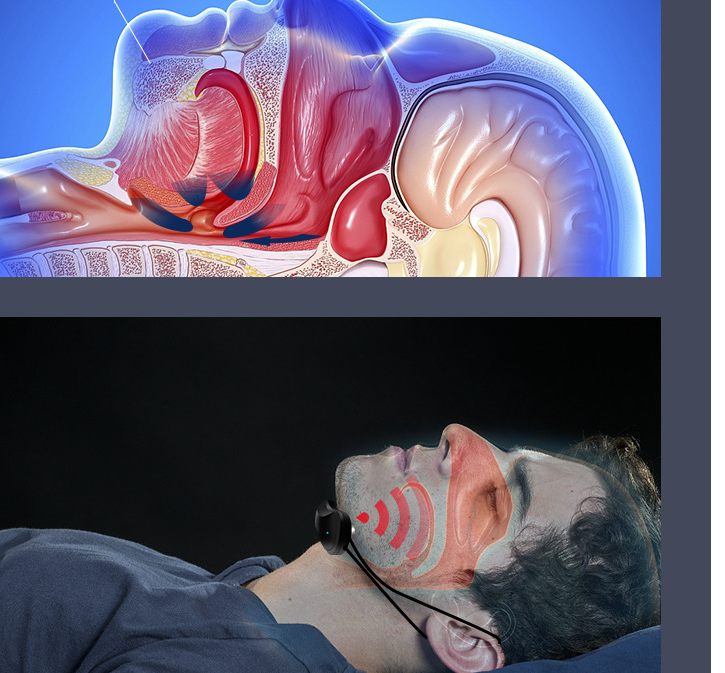

Intelligent Anti-snoring Device

Intelligent Anti-snoring Device

Pulse frequency: 10HZ-1500Hz